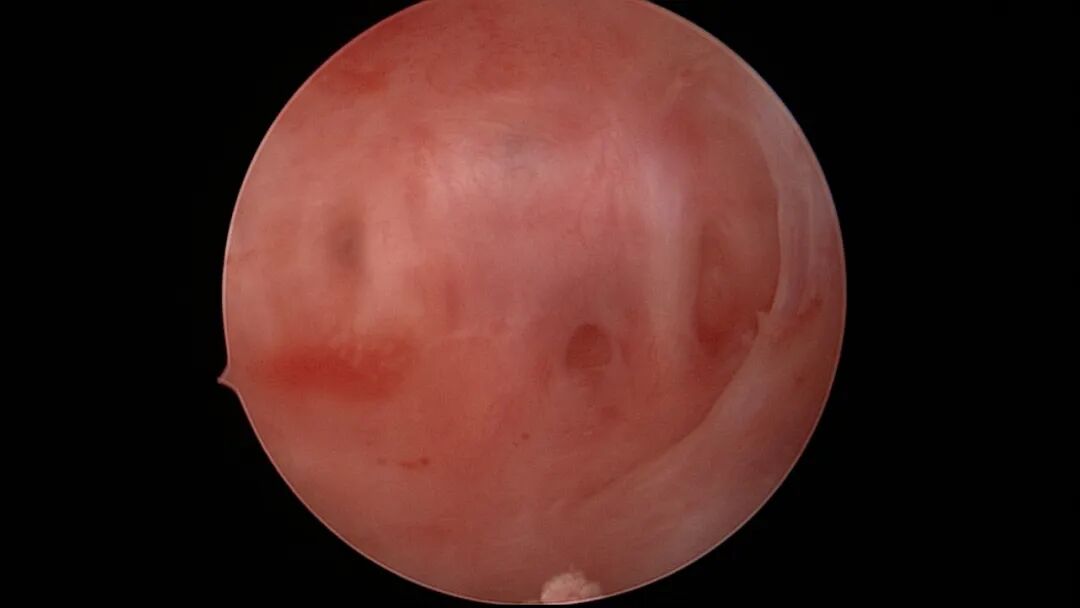

第八次宫腔镜:2025年7月宫腔镜二探取球囊,宫腔形态正常,双侧输卵管开口可见,内膜薄,片状充血。球囊在宫腔具有持续塑形作用,分粘术中没有显露的右侧输卵管开口已自我修复。